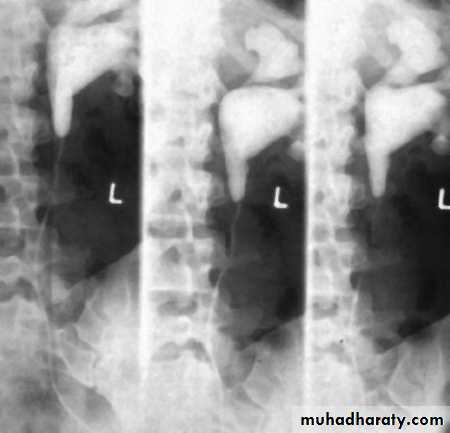

14- Retrocaval

16- Retrocaval